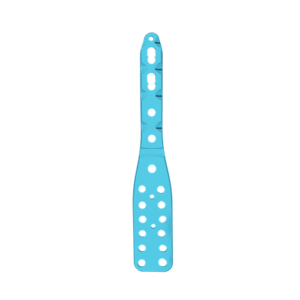

CLAVO PARA ARTRODESIS DE TOBILLO

El clavo para artrodesis de tobillo está diseñado para deformidades y artritis graves del pie y el tobillo.